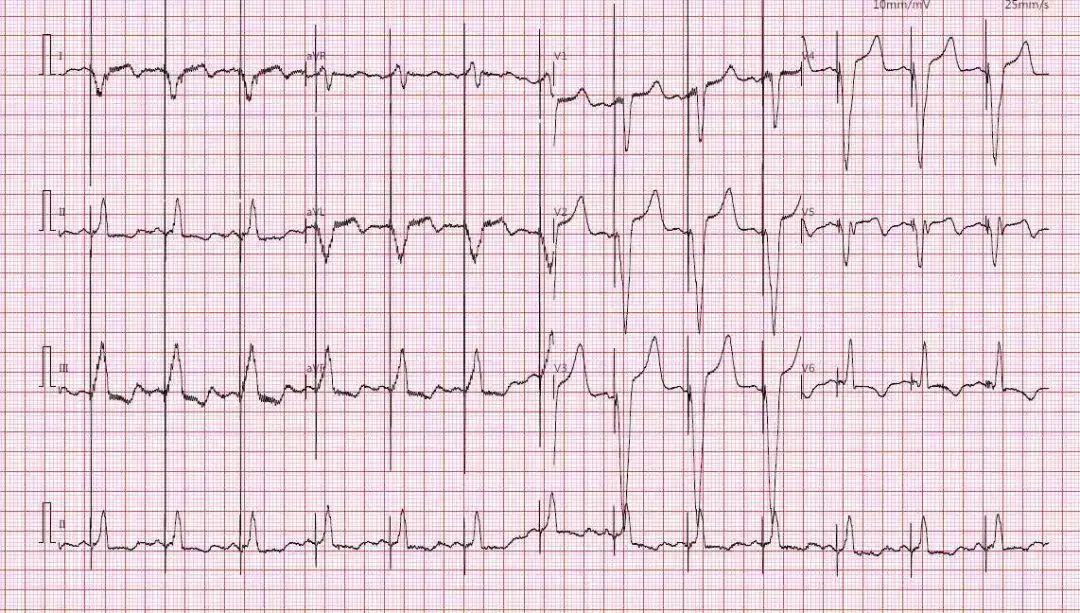

患者75岁老年女性,因“反复胸闷气促多年”确诊为扩张型心肌病,完全性左束支传导阻滞(QRS波160ms),心功能不全(EF 30.4%),曾在当地医院接受传统心脏再同步化除颤器(CRT-D)植入。术后患者胸闷气促仍反复发作,至本院就诊时心电图起博后QRS波宽度180ms,心脏超声显示左室内收缩不同步SPWMD 391ms,多巴酚丁胺试验提示心脏功能可。患者心肌NT-proBNP明显升高为2790 pg/mL。起博器程控提示CRTD能源近耗竭,冠状窦左室导线阈值过高(5V/1.2ms)。锁骨下静脉造影提示患者左锁骨下静脉近中段闭塞。面对挑战,心内科潘小宏主任医师在临时起搏保护下局麻下切开原脉冲发生器囊袋,分离原起博和ICD导线后以锁定钢丝和扩张鞘顺利拔出左心室电极导线和心室导线,剪去ICD导线头端,暴露内芯,植入锁定钢丝至接近ICD电极头端,沿锁定钢丝及电极导线扩张鞘前行至锁骨下静脉中段后难以继续推进,改为置入准分子激光鞘管,在X线透视指引下逐渐前行将ICD导线和粘连的左锁骨下静脉分离,直至上腔静脉和右心房上部,顺利拔除ICD电极导线,留置准分子激光鞘外鞘,沿鞘管置入两根泥鳅导丝,撤出准分子激光鞘外鞘。沿导丝植入7F长鞘管,根据标测到的希氏束位点及多导联心电监测图形,在希氏束315鞘指引下植入3830电极导线至左束支区城,此时测量QRS 波群宽度为112ms,阻抗感知國值等参数均良好,固定电极导线,将心房导线电极植入右心耳处。